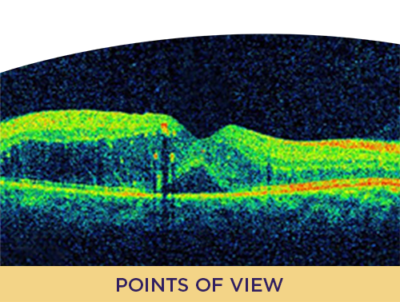

OCT Biomarkers and Response Prediction With IVT Anti-VEGF for DR/DME